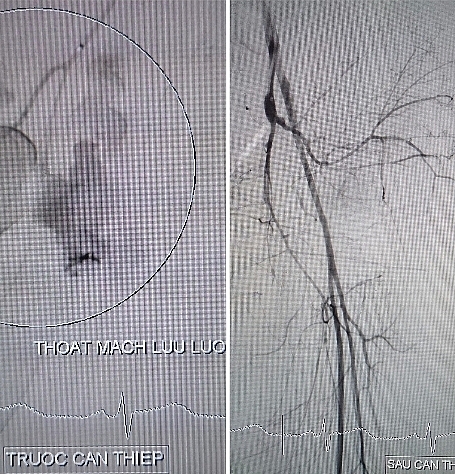

Hình ảnh thoát mạch trước can thiệp và sau can thiệp.

Các bác sĩ can thiệp mạch tiến hành chụp mạch số hóa xóa nền mạch máu vùng chậu phát hiện ổ thoát mạch từ nhánh động mạch chậu trong trái và tiến hành nút mạch cầm máu ổ thoát mạch lưu lượng lớn với thời gian 10 phút (bơm tắc bằng hỗn hợp keo Histoacryl).

Sau can thiệp nút mạch thành công, tình trạng huyết động bệnh nhân cải thiện tốt mạch rõ, huyết áp ổn định, bệnh nhân được chuyển hậu phẫu, điều chỉnh rối loạn đông máu và tiếp tục thực hiện các can thiệp tiếp theo.